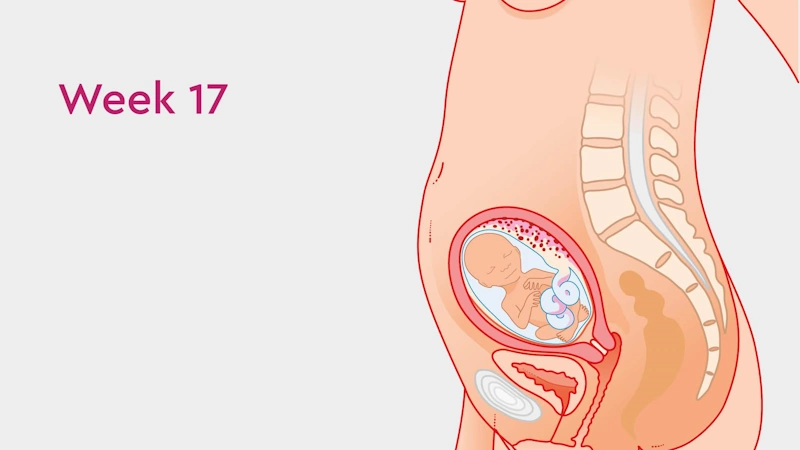

What Happens in the 17th Week of Pregnancy?

At 17 weeks pregnant, your baby is growing rapidly and your body is going through beautiful, visible changes.

Baby Development in Week 17 of Pregnancy

Your baby is now about 12.5 cm long (roughly the size of a pen) and becoming more active every day.

They can now move their hands and legs, touch their face, and even suck their thumb — practicing essential reflexes for life after birth.

The circulatory and urinary systems are functioning efficiently.

Your baby practices breathing movements by inhaling and exhaling small amounts of amniotic fluid.

This week, your baby is more active than ever — stretching, turning, and kicking gently inside your uterus.